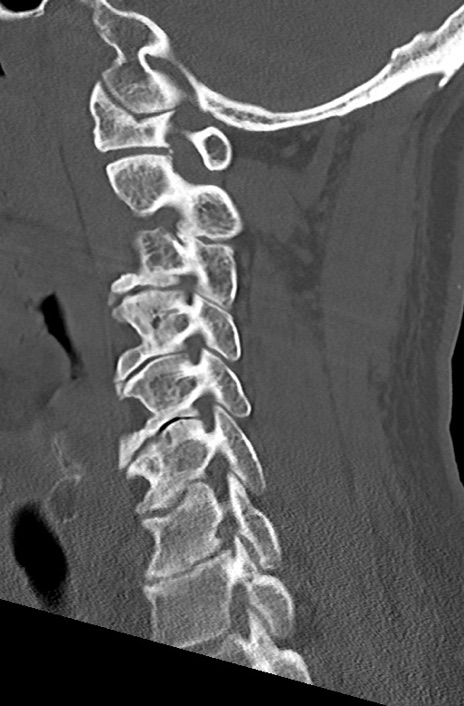

頚椎CT

矢状断像と横断像